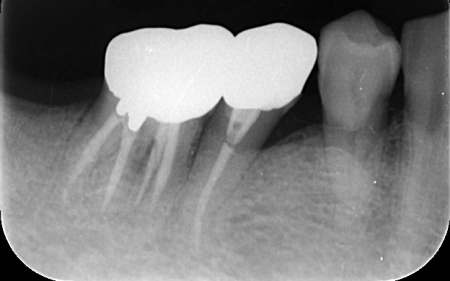

詳しく調べるためにレントゲン撮影を行った結果、どちらの歯も歯根が割れていることが確認できました。

3ヶ月後、インプラントと骨がしっかりと結合したことが確認できたため、被せ物を作製するための型取りを行います。

被せ物には、人工ダイヤモンドと呼ばれるほど高い強度をもつ、ジルコニアセラミックを使用したブリッジを製作しました。

後日、完成した被せ物を装着し、見た目や噛み合わせに問題がないことを確認して、治療を終了しています。